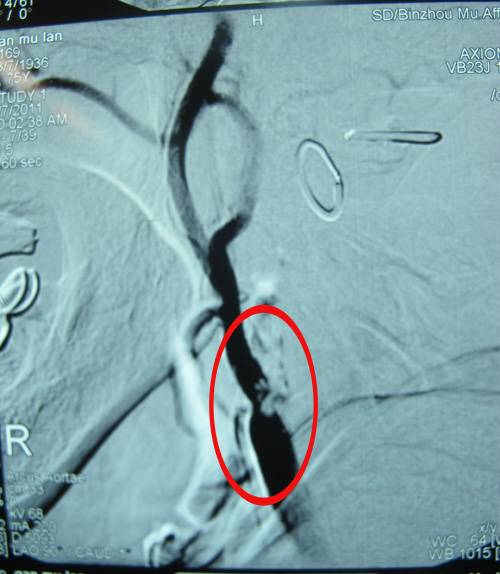

辅助检查:颅脑DSA:双侧颈动脉狭窄。

该患者TIA症状(发作性左上肢乏力、抖动)频繁发作1年,且有加重趋势,患者合并糖尿病、冠心病等危险因素。DSA检查示:双侧颈动脉狭窄。符合CEA手术指征。2011年3月29日,协作组张勤奕教授与安贞医院欧阳川教授应邀前往青岛顺利为其实施了右侧颈动脉内膜剥脱术。目前患者情况稳定,待恢复3个月左右再为其实施左侧手术。